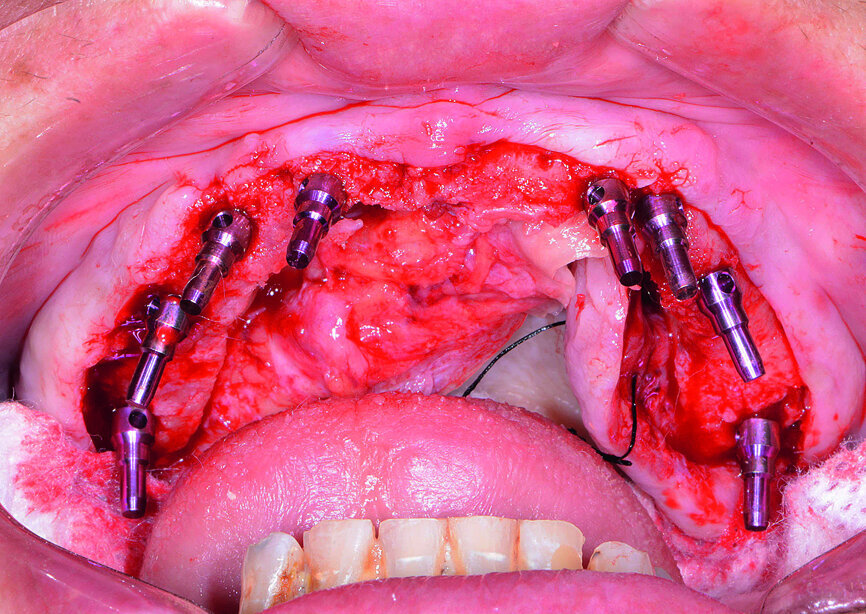

Fig. 13: Mandibular arch anaesthetised.

Fig. 14: Mandibular surgical guide stabilised.

Fig. 15: Implants and healing caps with surrounding grafting.

Next, the patient’s untreatable mandibular teeth (Fig. 13) were extracted using the Physics Forceps (GoldenDent), a flap was reflected, and an alveoloplasty was performed. A bone-supported guide was seated in order to control the location and angulation of the implant osteotomies (Fig. 14). As the Hahn Tapered Implants were threaded into place, their deep, sharp threads engaged the walls of the socket sites and helped maintain proper position toward the lingual aspect. Because of anticipated tissue swelling as a result of the bone levelling procedure, 5 mm high healing abutments were connected to the implants in the lower arch (Fig. 15). The immediate dentures were soft-relined with Mucopren (Kettenbach) to seat over the Hahn Tapered Implant Healing Abutments, the hourglass shape and undercuts of which provided a degree of retention that enhanced dental function for the patient during healing (Fig. 16).